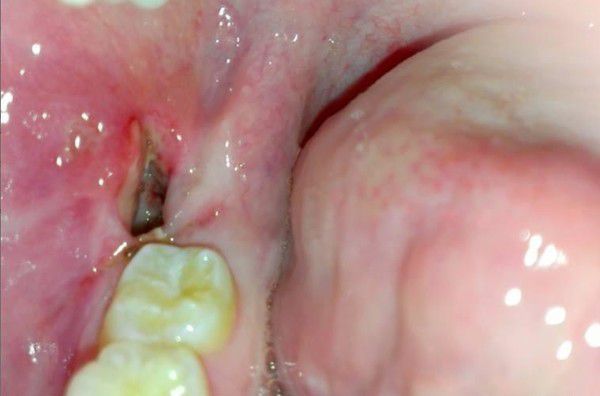

- Odsłonięty zębodół – brak skrzepu sprawia, że zębodół wygląda na pusty, a czasami widoczna jest odsłonięta kość. Może być pokryty szarawym nalotem, a otaczająca błona śluzowa staje się zaczerwieniona, obrzęknięta i bolesna przy dotyku.

Po usunięciu zęba w zębodole tworzy się skrzep krwi, który pełni rolę naturalnego opatrunku – chroni ranę przed zakażeniem i stanowi podstawę do jej prawidłowego gojenia. Skrzep osłania odsłoniętą kość, zabezpiecza zakończenia nerwowe oraz umożliwia stopniową odbudowę tkanek od wewnątrz.

Skrzep krwi jest więc strukturą tymczasową, ale niezbędną dla rozpoczęcia procesu regeneracji. Jego utrata lub rozpad prowadzi do odsłonięcia kości, co uniemożliwia gojenie i może doprowadzić do rozwoju zapalenia zębodołu.